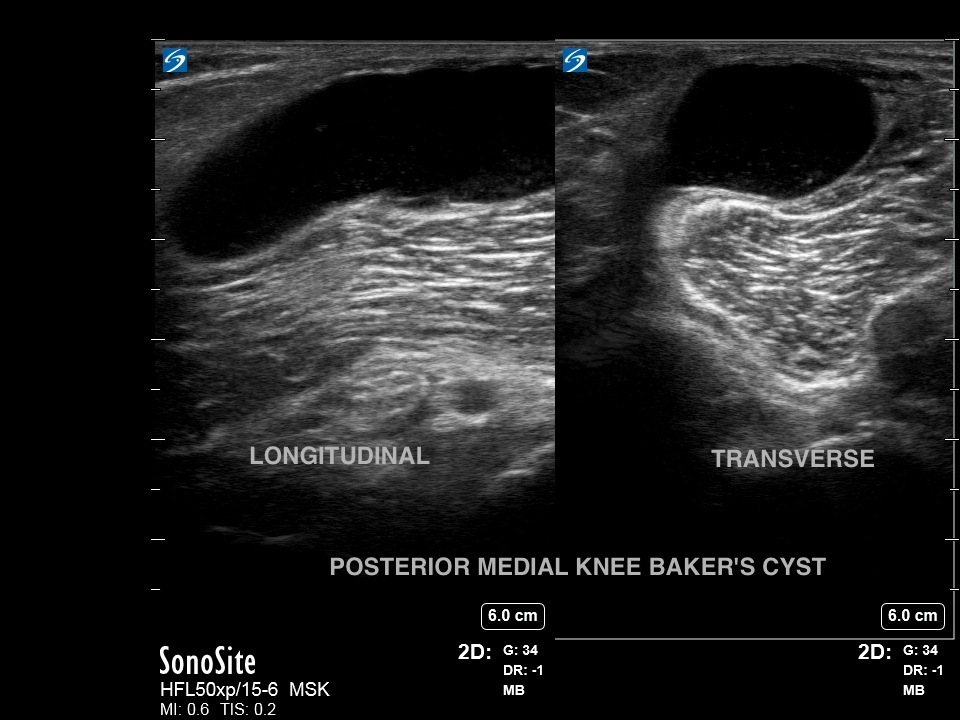

膝ベーカー嚢胞画像